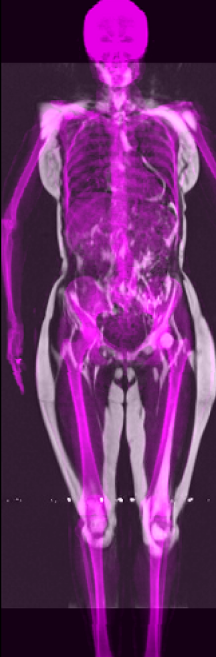

Recently, the use of diffusion-based models for image inverse problems has shown great success [63, 18, 35, 51, 40, 52]. This motivated our X-Diffusion to investigate learning volumes instead of images. In this light, our X-Diffusion proposes a novel architecture to allow learning on 3D volumetric data by view-dependent cross-sections. This allows for full MRI generation with unprecedented accuracy from a single MRI slice, multiple slices, or even from DXA image if paired data is available (see Figure 1). To the best of our knowledge, X-Diffusion is the first work to successfully generate detailed MRI volumes from a single DXA scan, bridging the gap between two common data modalities in medical imaging. It is important to note that the generated MRIs are not clinical replacements for true MRIs, but could provide a quick, affordable, and informative “pseudo-MRI" before conducting a full MRI examination.

3.4 DXA to MRI Volume Generation

DXA is a single image data modality that is similar to X-ray but includes other non-bony information such as tissue mass [67]. It measures bone mineral density and body fat composition. The radiation level is low enough that it is acceptable for conducting studies of healthy participants, such as the UK Biobank. In order to leverage X-Diffusion to synthesize the MRI volume from a single DXA (as in Figure 3), they have to be aligned, and registered. Note that, the size of the DXA does not match the MRI () and the scans are not registered. The two modalities in UK BioBank were not taken simultaneously but close in time hence why we believe registration is feasible for these two sequences as illustrated extensively in [79].

In order to tackle this domain gap, we leverage a registration network [79] paired with a X-Diffusion to achieve DXA to MRI slice generation. [79] introduced a multi-modal image-matching contrastive framework, that is able to learn correspondences between DXA and middle coronal MRI slices. These networks extrapolate the DXA scan by a transform to the coronal MRI slice by harnessing the embedded patterns and features of the DXA and the coronal MRI mid-slice. X-Diffusion is then trained on the registered DXA () and corresponding MRI slices in () in the target MRI volumes and is able to produce precise MRI volumes that align with the DXA scans (see Figure 5 left). The other details are similar to Section 3.2 and Section 3.3.

Notably, X-Diffusion achieves state-of-the-art dB for a few input slices while baselines require more than 60 input slices to achieve similar performance (Figure 7). The margin is more than 12 dB PSNR for the 1-slice input in both the BRATS and the UK Biobank benchmarks (see Table 1 and Figure 6). For reference, two randomly sampled MRIs from UK Biobank would have a PSNR of 15.95 dB 0.36 (on 4800 randomly sampled examples). Omitting the preprocessing step of alignment DXA to MRI, leads to a drop of PSNR on average by 2.87 dB (29.01 dB 26.14 dB). The slices from 3D reconstructed volumes at varying depths and axis of rotation, visually match the ground truths for both brain and whole-body scans (see Figures 4 and 5 left). We also plot the error map (Figure 3) and the spread of the error (Figure 5 right) of such X-Diffusion generations to highlight the differences with the ground truth MRIs.